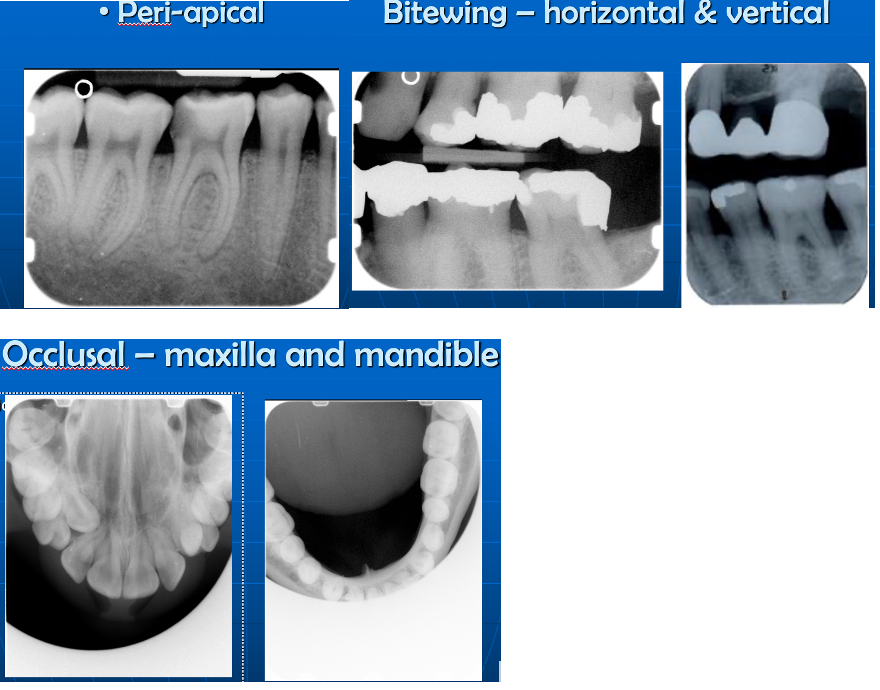

What are the Intra-oral x-rays?

What Film size would you use for Bitewing - vertical or horizontal?

Adult – “2” only

Child – over 10 – “2”

Child – under 10 – “0” or “1”